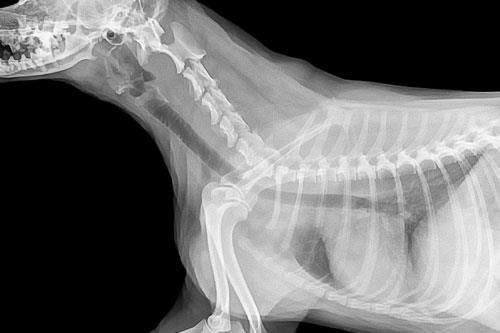

RÖNTGEN

- Diagnostik für die orthopädische Chirurgie

- Routine bei aktuen Erkrankungen

- Durchführung u.a. bei Baucherkrankungen oder Brustkorberkrankungen